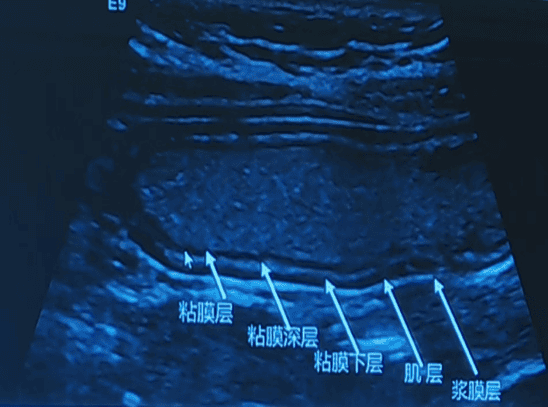

可清晰显示胃肠壁层次结构、厚度,能判断病变所侵犯层次及累及范围,还可以动态观察病变的实时变化,图像层次清晰,细节分辨能力高,有助于患儿消化道疾病(如先天性肥厚性幽门梗阻、阑尾炎、腹型紫癜、炎性肠病等)的临床快速诊断,更快速有效地进行下一步诊治,减少患儿的就诊及住院时间。

我院是整个衡阳市唯一一家开展胃十二指肠超声造影检查的医院, 于2024年开展至今,已经完成近200余例,具有安全、无创伤、无痛苦、动态、重复性好等特点。

该技术优势明显:安全无创伤、无痛苦,检查过程动态直观,重复性好且无不良反应,能有效助力胃十二指肠相关疾病的诊断与筛查。